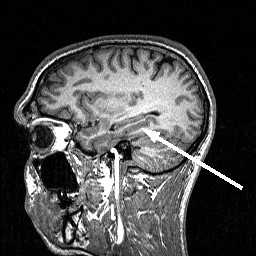

Границей между средним мозгом и мостом служит верхняя борозда, а с продолговатым мозгом - нижняя борозда моста. Мост имеет характерную выступающую вперед переднюю часть. Задняя поверхность моста является продолжением продолговатого мозга. У верхней границы моста между его брюшком и средней ножкой мозжечка, начинаются тройничные нервы (n. trigeminus, V пара). Они хорошо видны на поперечных МР срезах , так как идут горизонтально вперед и имеют толщину около 5 мм. Тройничный нерв делится на 3 ветки - зрительную (1), верхнечелюстную (2) и нижнечелюстную (3). Все они идут вперёд в Мекелеву полость к тройничному ганглию. Отсюда 3 ветка уходит вниз через овальное отверстие, а 1 и 2 ветки идут через кавернозный синус, вдоль его латеральной стенки. Затем, 1 ветка входит в орбиту через верхнее отверстие, а 2 ветка выходит из полости черепа через круглое отверстие.

МРТ головного мозга. Аксиальный срез. Тройничные нервы (стрелка).